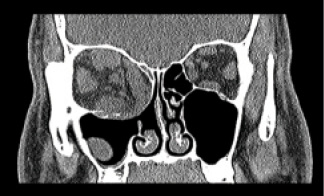

Figure 9. CT scan of the patient’s orbits prior to radiation and decompression.

Figure 10. B-scans of the orbit at postoperative week 4 after trabeculectomy, showing choroidals and tenting of the sclera secondary to orbital congestion.

The patient underwent trabeculectomy of the right eye due to high IOP on maximal medical therapy. In the immediate postoperative period, he had a diffuse bleb, IOP in the low teens, and preservation of baseline visual acuity. However, around postoperative week 2, the right eye developed significant chemosis and proptosis from reactivation of his thyroid eye disease and orbital congestion that required immediate pulse therapy with intravenous methylprednisolone sodium, followed by weekly intravenous methylprednisolone sodium.

The orbital congestion and pressure were pushing his globe forward and encouraging outflow through the trabeculectomy site, causing a shallow anterior chamber. At postoperative week 4, visual acuity was reduced to hand motions, and radiation of the orbit was performed to reduce the orbital congestion (Figures 9 and 10). At postoperative week 8, orbital decompression was performed endoscopically, which improved the proptosis and chemosis. At 5 months after initial presentation to our center, the proptosis in the right eye was improved, the IOP was 14 mm Hg, the chamber continued to be moderately shallow with peripheral choroidals, and visual acuity was hand motions with a dense posterior subcapsular cataract. After cataract extraction, the patient’s visual acuity remained stable at 20/800.